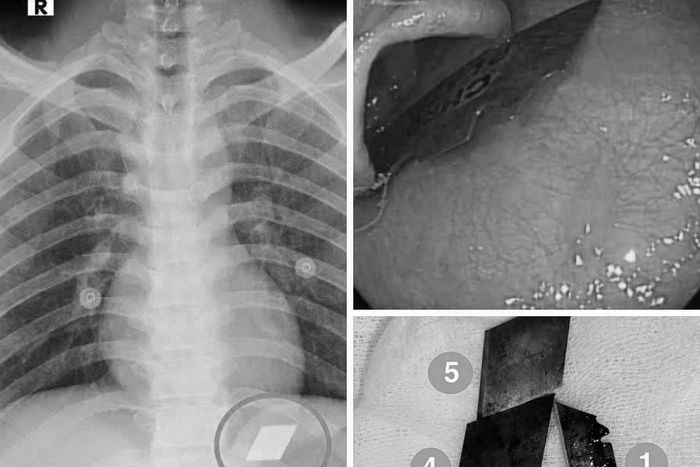

Qua thăm khám và chụp X-quang, các bác sĩ phát hiện dị vật cản quang tại vị trí dạ dày. Bệnh nhân lập tức được chỉ định nội soi cấp cứu. Dưới sự phối hợp chặt chẽ giữa ê-kíp nội soi và gây mê, các bác sĩ đã gắp thành công 4 lưỡi dao rọc giấy ra khỏi dạ dày và một phần lưỡi dao lam mắc tại vùng hạ họng - miệng thực quản.

Hình ảnh dị vật trong đường tiêu hóa. Ảnh: BVCC.